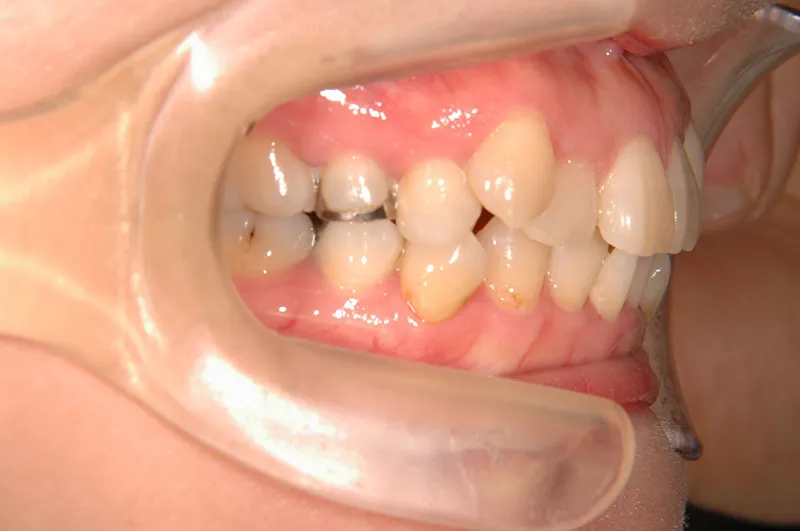

初診時年齢 40歳以上 (女性) 主訴 上下のがたがた・噛み合わない

診断名 叢生 装置名

状態 ガタガタ・でこぼこに生えている(叢生)

八重歯(叢生)

上下のがたがたと噛み合わない事を主訴に来院されました。

歯は抜かずに矯正治療しました。

治療回数35回、2年8ヶ月の治療期間で矯正治療を終了しました。